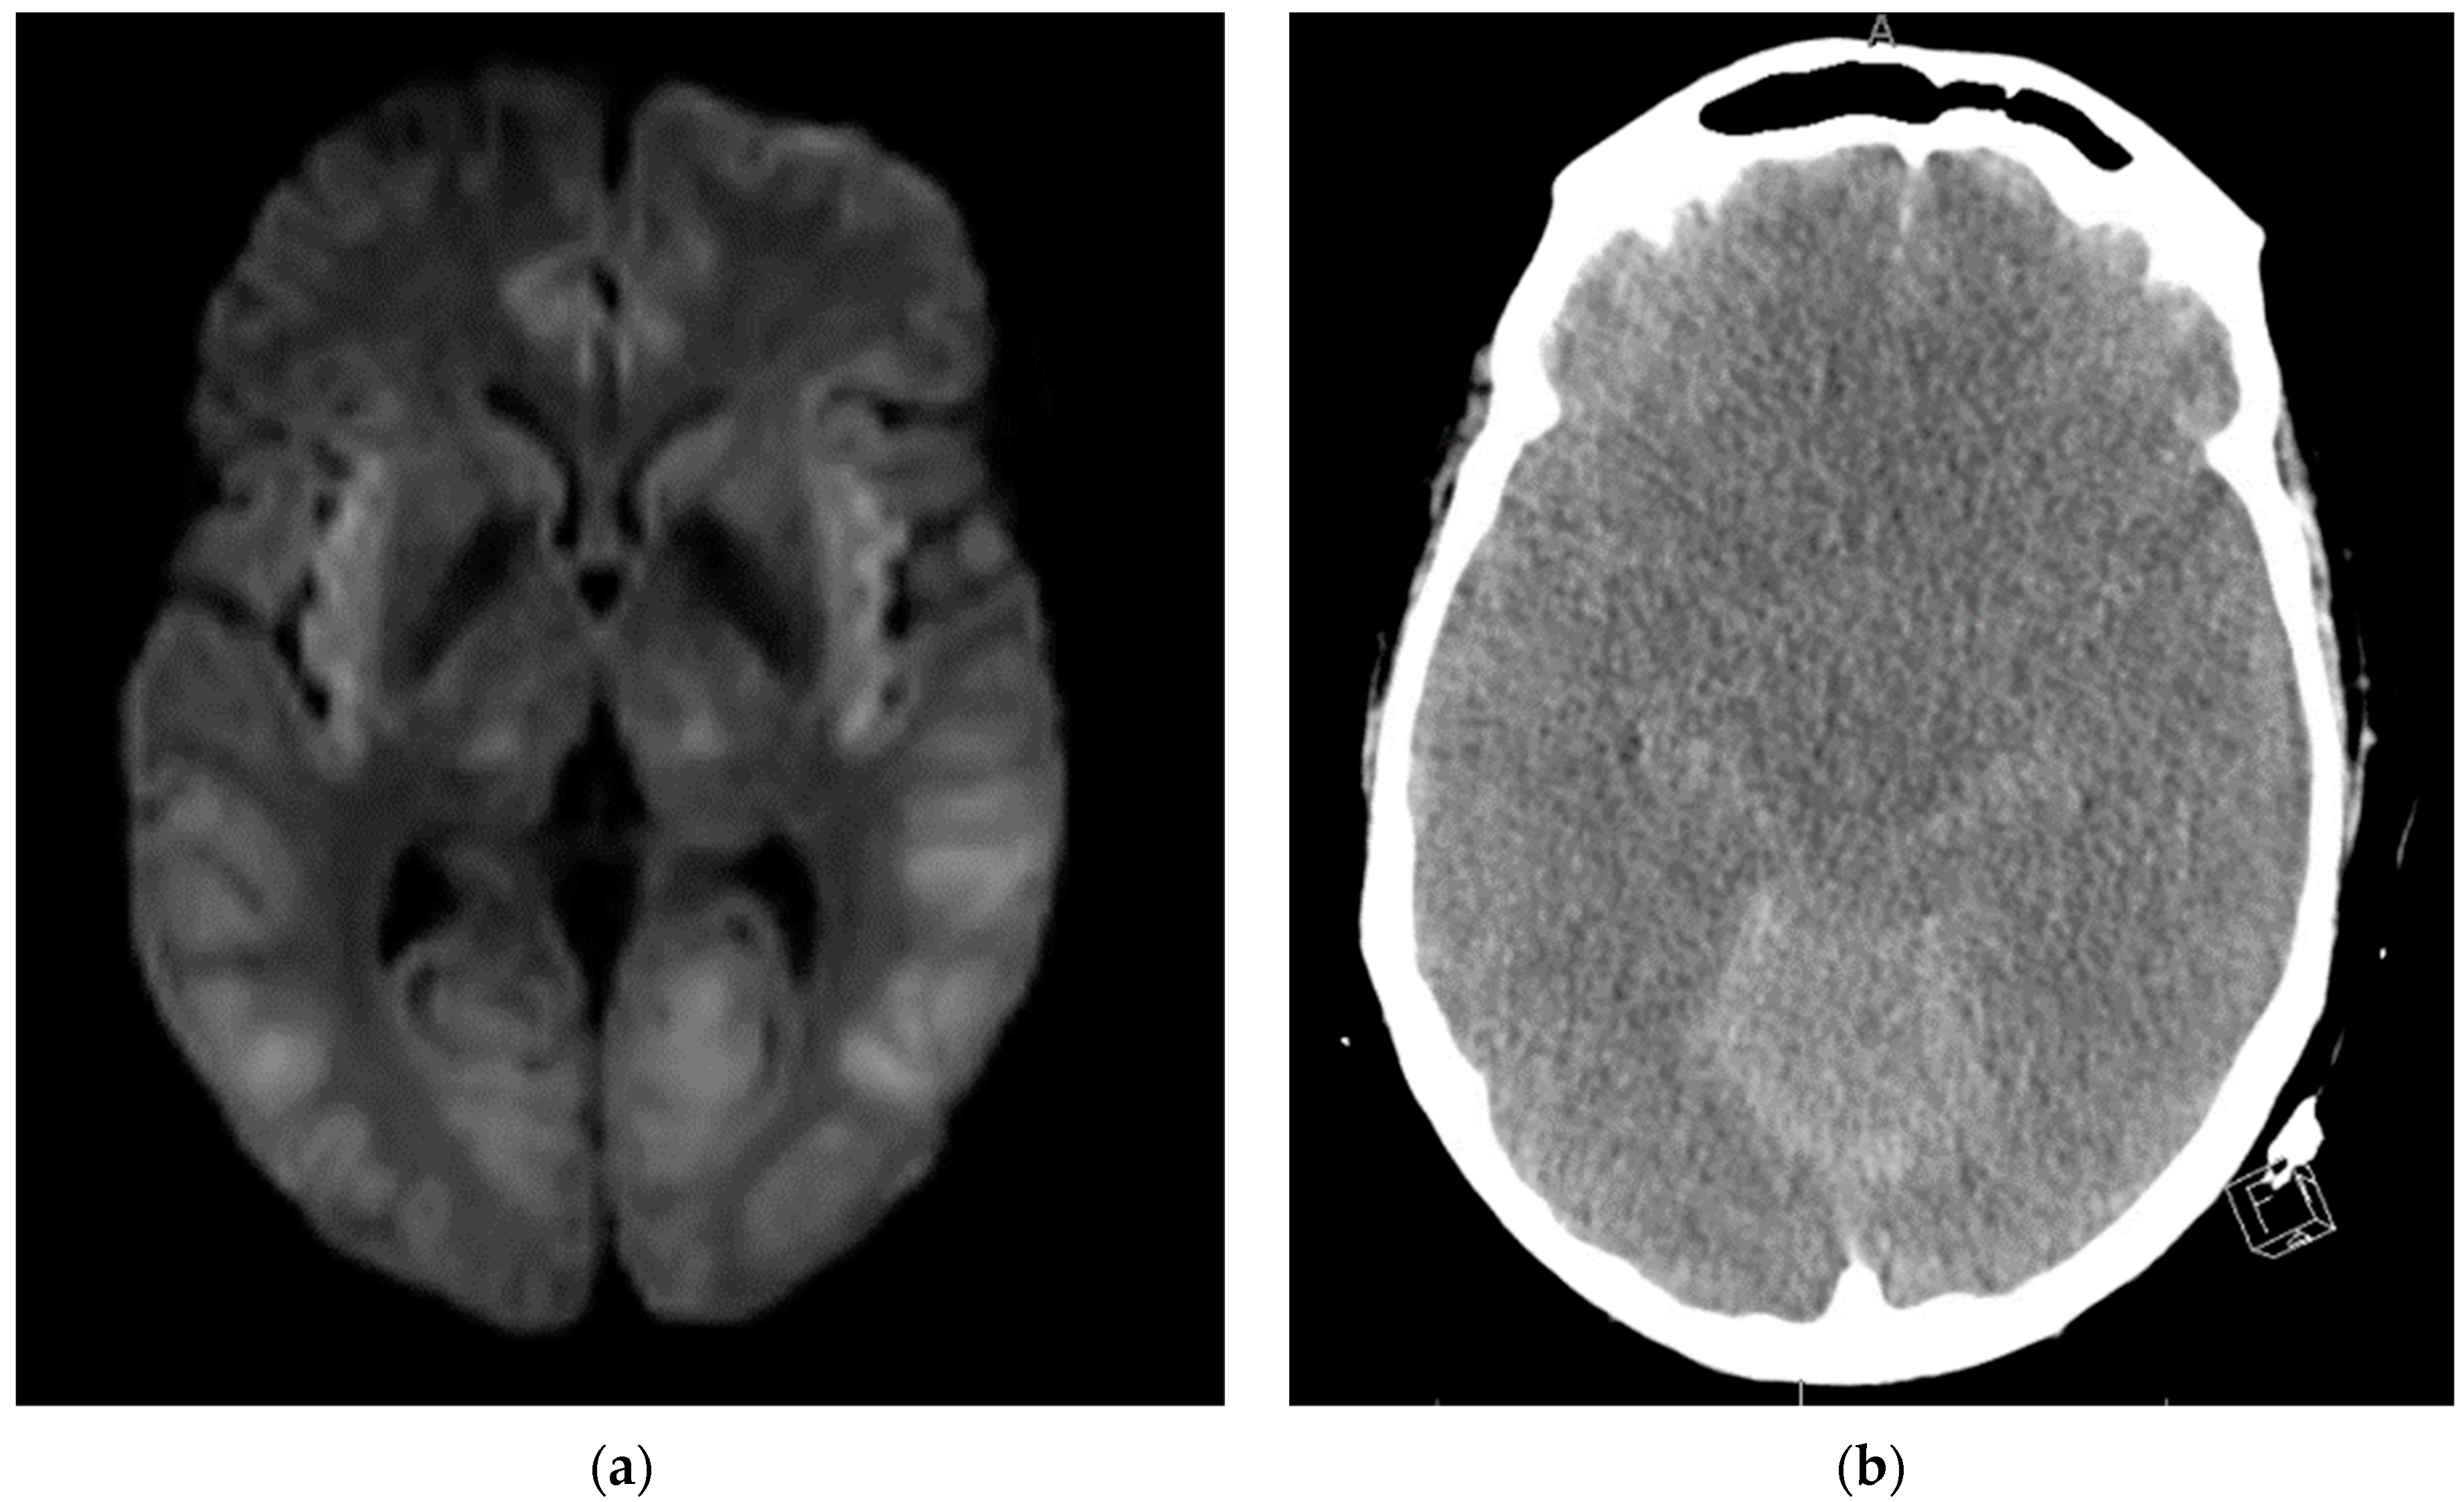

During EEG monitoring, the patient had a total of 19 recorded seizures. Three of the seizures were prolonged (lasting 15–30 min each) and had clinical signs of head jerking and facial twitching. All seizures showed bilateral occipital onset with rhythmic and repetitive sharps which evolved in both frequency and amplitude with right occipital predominance. There were 16 subclinical seizures recorded with bilateral occipital activities, and also with right occipital predominance. These findings were consistent with status epilepticus and the patient was loaded with IV levetiracetam and then started on a midazolam drip with burst suppression. Overnight the patient proceeded into non-convulsive status epilepticus (NCSE) and required IV lacosamide. He was on 10 mg/hr midazolam which was then weaned abruptly the following day. That night the patient emerged into convulsive status epilepticus and was re-bolused with midazolam, which was then increased serially up to 50 mg/hr with no effect over the next two hours. He was then loaded with fosphenytoin which for several hours resulted in dissipation of convulsive activity and <2.5 Hz Bi-PLEDs (bilateral-type periodic epileptiform discharges). Two hours later, the patient returned to NCSE with 1 Hz Bi-PLED activity noted. Ketamine was loaded at this point and all seizure activity stopped. EEG was noted flatlining and a head CT was obtained revealing profound edema (

Figure 4). The patient was examined and pronounced brain-dead.